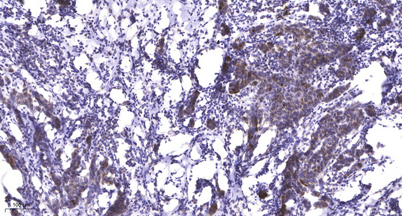

Immunohistochemical analysis of paraffin-embedded human Breast cancer. 1, Antibody was diluted at 1:200(4° overnight). 2, Tris-EDTA,pH9.0 was used for antigen retrieval. 3,Secondary antibody was diluted at 1:200(room temperature, 45min).